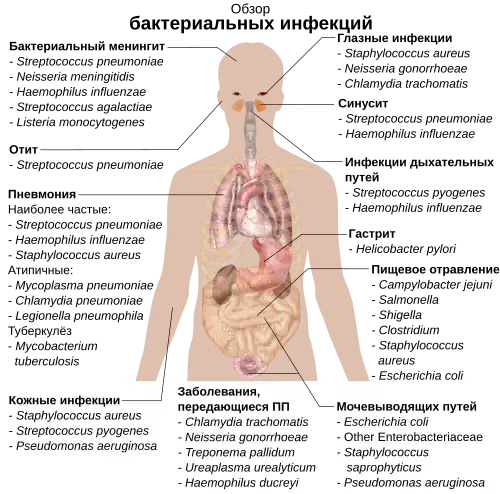

Патогены

Бактерии, паразитирующие на других организмах, называют патогенами. Патогенные бактерии являются причиной множества человеческих смертей и вызывают такие инфекции, как столбняк, брюшной тиф, дифтерия, сифилис, холера, пищевые отравления, проказа и туберкулёз. Патоген, вызывающий заболевание, может быть описан много лет спустя после описания самой болезни, как, например, произошло с Helicobacter pylori и язвенной болезнью желудка. Бактерии ответственны за многие болезни культурных растений (бактериозы), в числе которых пятнистость листьев[177], ожог плодовых культур и увядание. Бактериальную основу имеют такие заболевания домашнего скота, как паратуберкулёз, мастит, сальмонеллёз и сибирская язва[178][179].

Каждый патоген характеризуется особыми взаимодействиями с организмом хозяина. Некоторые возбудители, такие как виды родов Staphylococcus и Streptococcus, вызывают кожные инфекции, пневмонию, менингит и даже сепсис, системный воспалительный ответ, переходящий в шок, массивную вазодилатацию сосудов и заканчивающийся смертью[180]. При этом те же самые микроорганизмы входят в состав нормальной микрофлоры человека и зачастую обитают на коже и внутри полости носа, не вызывая никакого заболевания. Другие бактерии всегда вызывают болезнь, например, риккетсии, которые являются облигатными внутриклеточными паразитами и могут размножаться только внутри клеток организма-хозяина. Один вид риккетсий вызывает сыпной тиф, другой является возбудителем пятнистой лихорадки Скалистых гор. Другой род облигатных внутриклеточных паразитов, Chlamydia, включает возбудителей пневмонии, инфекций мочевыводящих путей и коронарной недостаточности[181]. Некоторые бактерии, такие как Pseudomonas aeruginosa, Burkholderia cenocepacia и Mycobacterium avium, являются оппортунистическими патогенами и вызывают заболевания преимущественно у людей, страдающих от иммунодефицита или муковисцидоза[182][183].

Бактериальные инфекции можно лечить антибиотиками, в числе которых выделяют бактерицидные препараты, которые убивают бактерии, и бактериостатики, только подавляющие их рост. Существует несколько классов антибиотиков, которые действуют на процессы, которые есть у бактерии-патогена, но нет у организма-хозяина. Так, антибиотики хлорамфеникол и пуромицин подавляют работу бактериальной рибосомы, но не действуют на эукариотические рибосомы[184]. Антибиотики используются не только в медицине, но и в животноводстве для стимуляции роста животных, что стало причиной повсеместного распространения устойчивости к антибиотикам в популяциях бактерий[185].